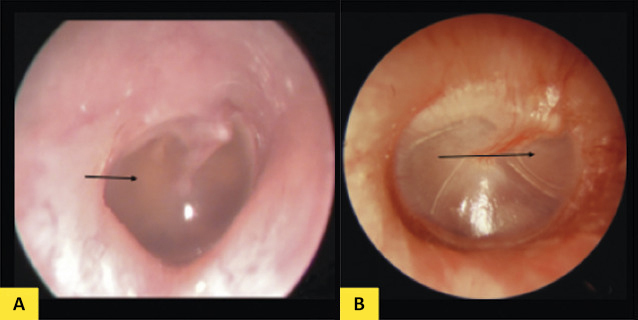

L’examen otoscopique (figure) met en évidence un épanchement plus ou moins abondant rétrotympanique responsable d’un aspect de rétraction de la membrane tympanique (de couleur variable : jaunâtre, parfois blanchâtre, parfois bleue) avec ou sans bulles, ou au contraire d’un bombement, traduisant un épanchement rétrotympanique aux mêmes caractéristiques avec une saillie des reliefs du marteau.

Le diagnostic différentiel otoscopique entre OMA et OSM n’est pas toujours aisé car il peut y avoir un épanchement dans les 2 cas ; c’est son aspect et l’association à une symptomatologie aiguë (otalgie ou fièvre) qui orientent le diagnostic. Cependant, des OMA récurrentes peuvent se chevaucher avec une OSM rendant le diagnostic plus difficile, notamment si une OSM est diagnostiquée quelques semaines après le dernier épisode d’une OMA récurrente.